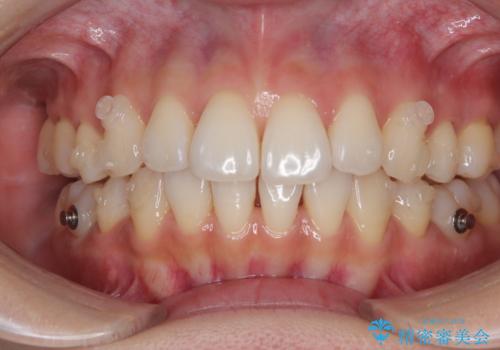

3. 終了時

3. 抜歯矯正の軽度後戻りを解消 インビザライン矯正の治療後